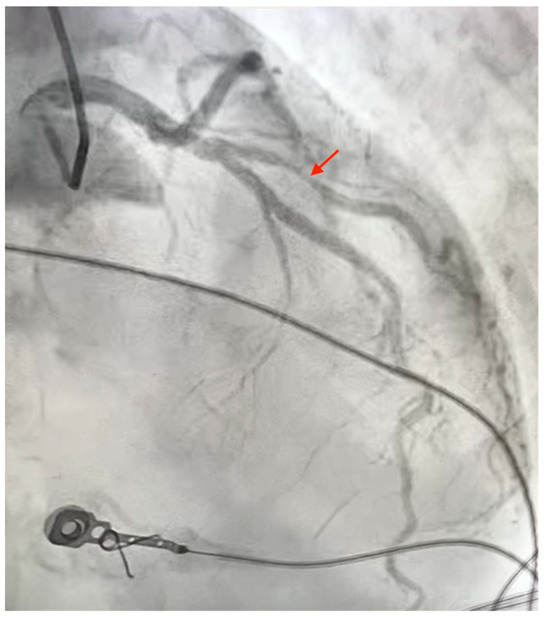

The Critical Role of Nutritional and Procedural Factors in CTO-PCI Patient Prognosis

by Gürkan Karaca, Ahmet Ekmekci, Ali Kimiaei, Seyedehtina Safaei, Aziz İnan Çelik and Metin Çağdaş

(1) Background: Chronic total occlusion percutaneous coronary intervention (CTO-PCI) is a complex, high-risk procedure compared to standard percutaneous coronary intervention (PCI). Scoring systems such as the Japanese Chronic Total Occlusion (J-CTO), European Chronic Total Occlusion (EuroCTO), and Prospective Global Registry for the Study [...] Read more.

(1) Background: Chronic total occlusion percutaneous coronary intervention (CTO-PCI) is a complex, high-risk procedure compared to standard percutaneous coronary intervention (PCI). Scoring systems such as the Japanese Chronic Total Occlusion (J-CTO), European Chronic Total Occlusion (EuroCTO), and Prospective Global Registry for the Study of Chronic Total Occlusion Intervention (PROGRESS-CTO) evaluate lesion difficulty and predict outcomes. Nutritional status, measured by the Prognostic Nutritional Index (PNI), may also affect procedural success and long-term survival. The objective of this study was to evaluate the combined impact of procedural complexity and nutritional status on the clinical outcomes of patients undergoing CTO-PCI. (2) Methods: We analyzed 118 patients undergoing CTO-PCI between May 2021 and March 2022. Procedural complexity was assessed using the J-CTO, EuroCTO, and PROGRESS-CTO scores, while nutritional status was evaluated using the PNI. Primary outcomes included all-cause mortality and repeat revascularization, which were analyzed using Cox proportional hazards regression and Kaplan–Meier survival analyses. (3) Results: Adverse outcomes occurred in 25 patients (mortality: 17; revascularization: 8). Patients with adverse outcomes had significantly lower left ventricular ejection fraction (LVEF) (46 ± 13.7% vs. 52.1 ± 10.5%, p < 0.001), lower PNI (p < 0.001), and higher J-CTO, EuroCTO, and PROGRESS-CTO scores (all p < 0.05). A PNI cut-off value of 46 predicted mortality with a sensitivity of 70.6% and specificity of 75.2% (area under the curve [AUC] = 0.739, p = 0.001). Multivariable analysis identified LVEF (hazard ratio [HR] 0.966, p = 0.036), J-CTO score (HR 1.598, p = 0.027), and PNI (HR 0.925, p = 0.022) as independent predictors of mortality. (4) Conclusion: Both procedural complexity and nutritional status significantly influence outcomes following CTO-PCI. Incorporating PNI together with procedural complexity scores into pre-procedural assessments may enhance risk stratification and optimize patient management. Full article

Figure 1